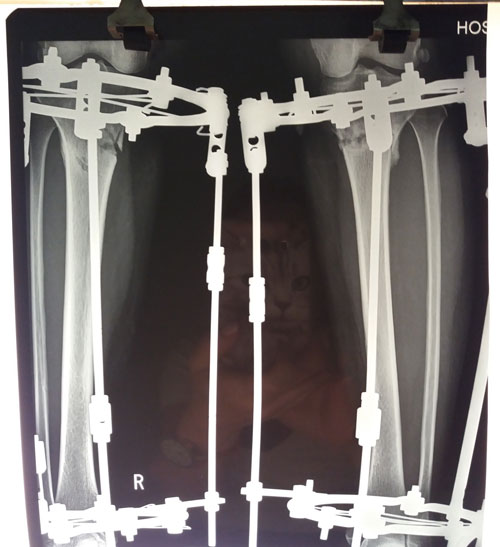

Исходник - 36 лет. Актау.

Дата операции - 19.06.2018г.

Дата снятия аппаратов 19.09.2018г.

Срок лечения 90 дней.